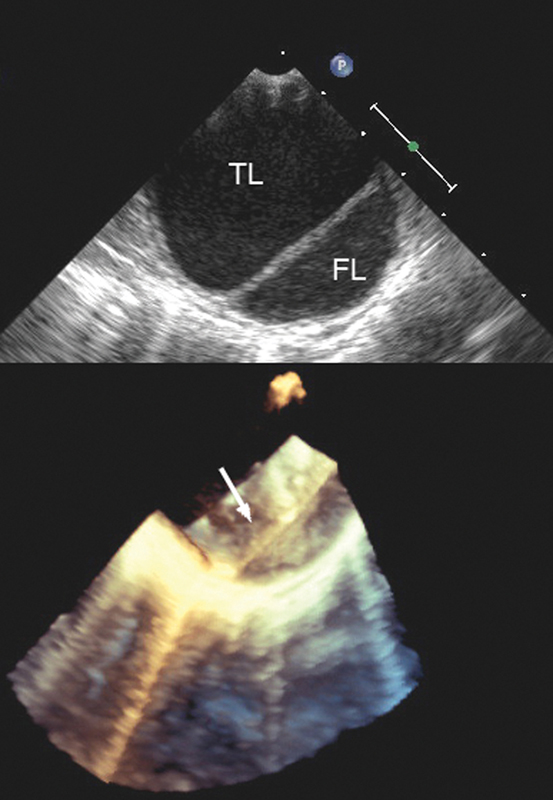

فحوصات تشخيصية لبعض امراض القلب والشرايين التاجية